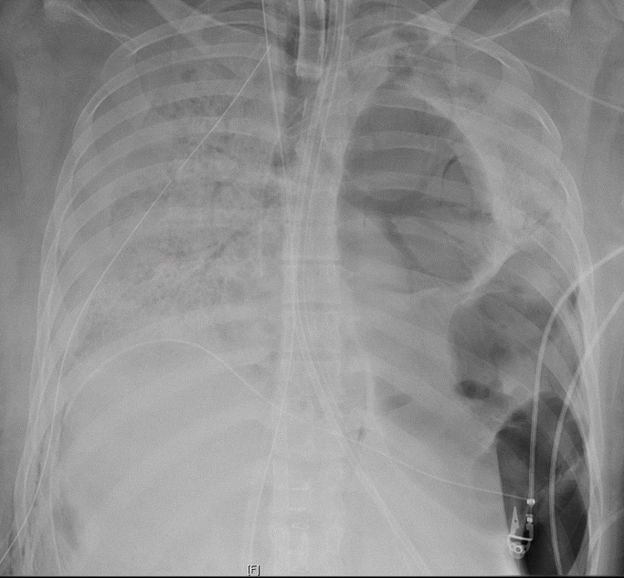

Quando os testes comprovaram que seu organismo finalmente estava livre de coronavírus, os pulmões já apresentavam danos irreversíveis, e os médicos decidiram pelo transplante.

Bharat afirma que, apesar de transplantes do tipo geralmente levarem cerca de sete horas, essa cirurgia teve duração de dez horas, devido à complexidade e ao estado dos pulmões da paciente, que apresentavam buracos "como um queijo suíço" e estavam colados aos tecidos e órgãos próximos.